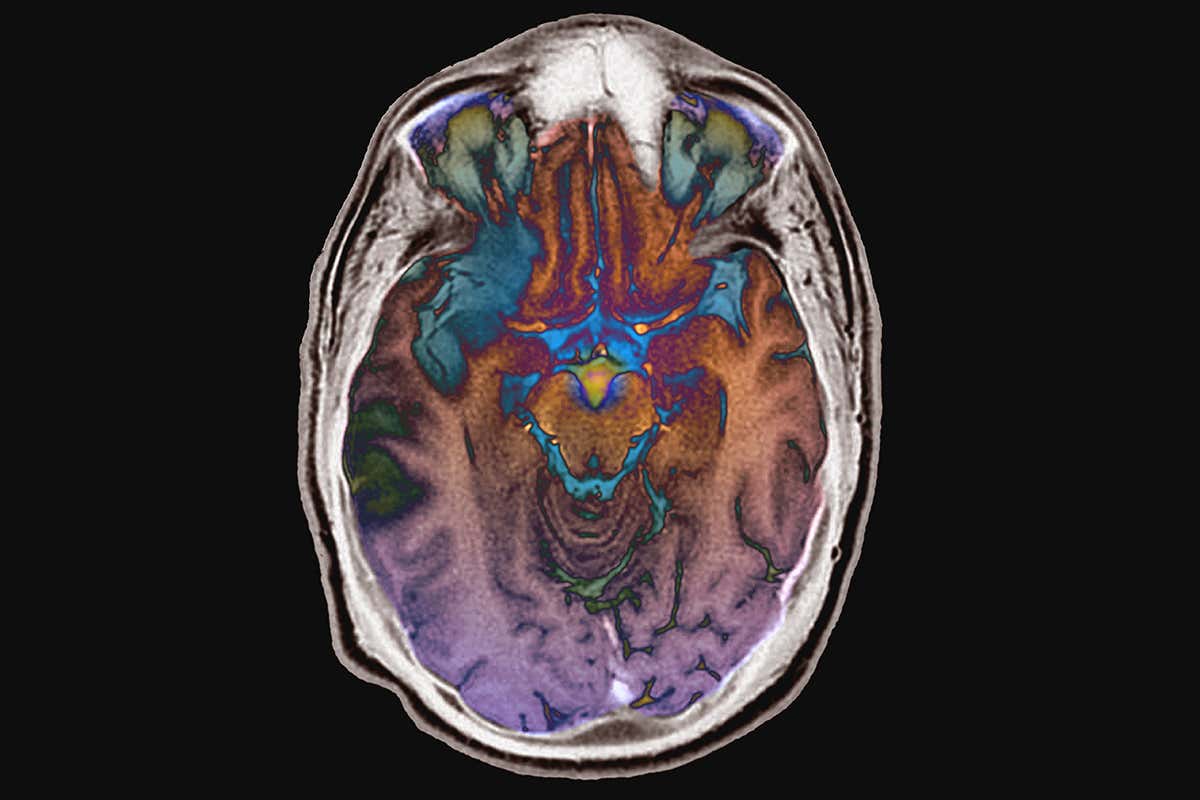

The brain can rewire itself Description:ZEPHYR/SCIENCE PHOTO LIBRARY